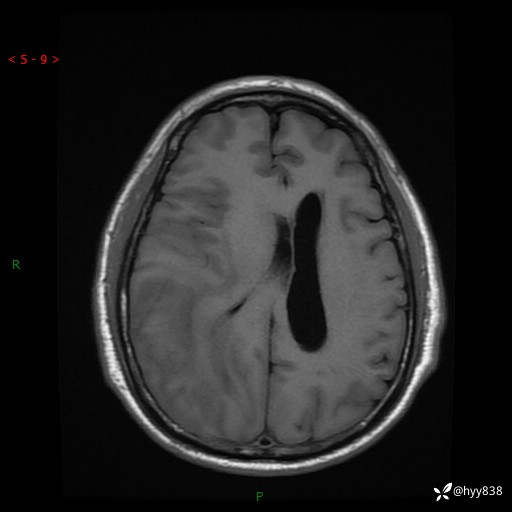

患者性别:男

患者年龄:56岁

简要病史:外院CT提示脑膜瘤,为进一步诊治来我院

临床诊断:颅脑占位

颅脑MRI平扫+增强